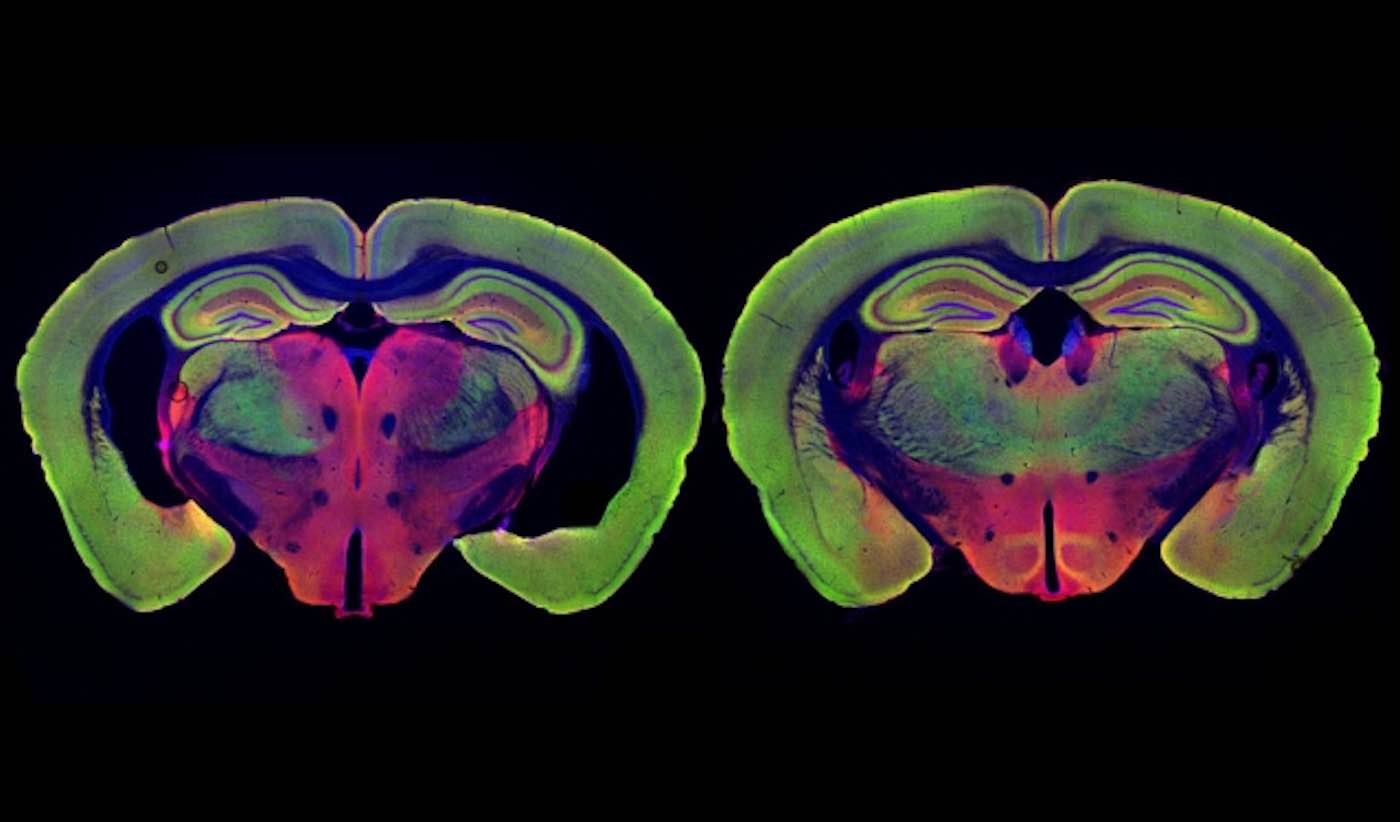

Photo by Chinnakkaruppan Adaikkan / MIT News

In their new study, the researchers wanted to delve deeper into how these beneficial effects arise. They focused on two different strains of mice that are genetically programmed to develop Alzheimer’s symptoms. One, known as Tau P301S, has a mutated version of the Tau protein, which forms neurofibrillary tangles like those seen in Alzheimer’s patients. The other, known as CK-p25, can be induced to produce a protein called p25, which causes severe neurodegeneration. Both of these models show much greater neuron loss than the model they used for the original light flickering study, Tsai says.

MORE: Blue Light Reduces Blood Pressure, Just as Effectively as Medication – UK Study

The researchers found that visual stimulation, given one hour a day for three to six weeks, had dramatic effects on neuron degeneration. They started the treatments shortly before degeneration would have been expected to begin, in both types of Alzheimer’s models. After three weeks of treatment, Tau P301S mice showed no neuronal degeneration, while the untreated Tau P301S mice had lost 15 to 20 percent of their neurons. Neurodegeneration was also prevented in the CK-p25 mice, which were treated for six weeks.